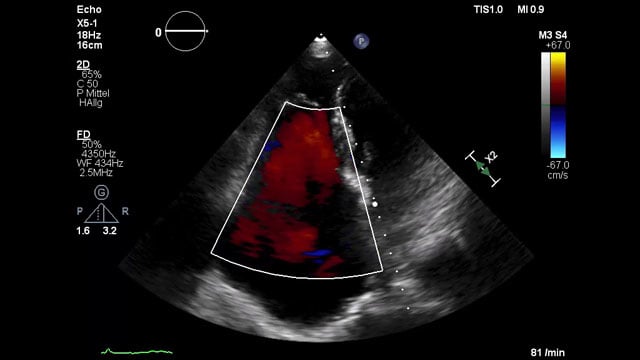

Severe MR in a high-risk patient with a suboptimal anatomy for M-TEER: what other options can we find?

Multimodality imaging reveals fibro-calcific leaflet disease, restricted motion, and a short posterior leaflet, making him a suboptimal candidate for M-TEER and prompting consideration of transcatheter mitral valve replacement. How would you treat?

A challenging valve-in-valve scenario in a patient with prior aortic coarctation repair

16 Feb 2026

A 79-year-old with a degenerated aortic bioprosthesis after complex coarctation surgery challenges conventional strategies. Which access route would you choose?